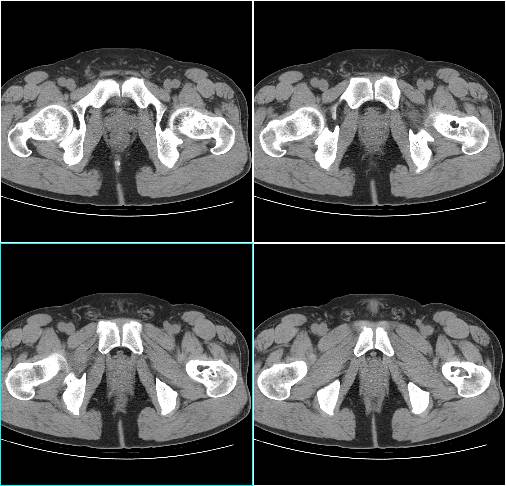

X线特征相当典型,容易作出诊断。病变位于长骨干骺端骨干的内侧,距骺板3~4cm处,未累及后者。病灶1~5cm大小不等,有的可达10cm。病变为圆形或椭圆形、偏心性生长,与骨长轴一致,但有向整个骨侵及倾向。病损内部常呈分叶状,骨皮质变薄,而髓侧边缘硬化,界限清晰。位于皮质骨附近者,从一侧突出骨外,表面骨质轻度扩张,骨质变薄。位于股骨等粗大骨内者可偏心性生长,位于腓骨等细小骨者可充满髓腔,表面骨质轻微变薄。肿瘤基底与髓腔边界处骨质轻微硬化,常呈肥皂泡沫状,可合并病理骨折。